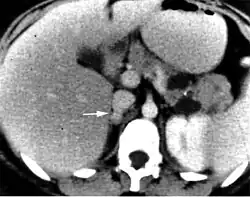

An adrenal incidentaloma is an adrenal tumor found by coincidence without clinical symptoms or suspicion. It is one of the more common unexpected findings revealed by computed tomography (CT), magnetic resonance imaging (MRI), or ultrasonography.[18][19] Adrenal incidentalomas often secrete cortisol and require thorough clinical evaluation.[19][20]

Management of incidentalomas include evaluation by a endocrinologist or endocrine surgeon.[14] Tumors under 3 cm are generally considered benign and are only treated if there are grounds for a diagnosis of Cushing's syndrome or pheochromocytoma. Radiodensity helps with estimating the risk of malignancy in a tumor. A tumor of 10 Hounsfield units or less on an un-enhanced CT is likely a lipid-rich adenoma.[21]

On CT scan, benign adenomas typically are of low radiographic density (due to fat content) and show rapid washout of contrast medium (50% or more of the contrast medium washes out at 10 minutes). If the hormonal evaluation is negative and imaging suggests benign, follow-up should be considered with imaging at 6, 12, and 24 months and repeat hormonal evaluation yearly for 4 years.[22]